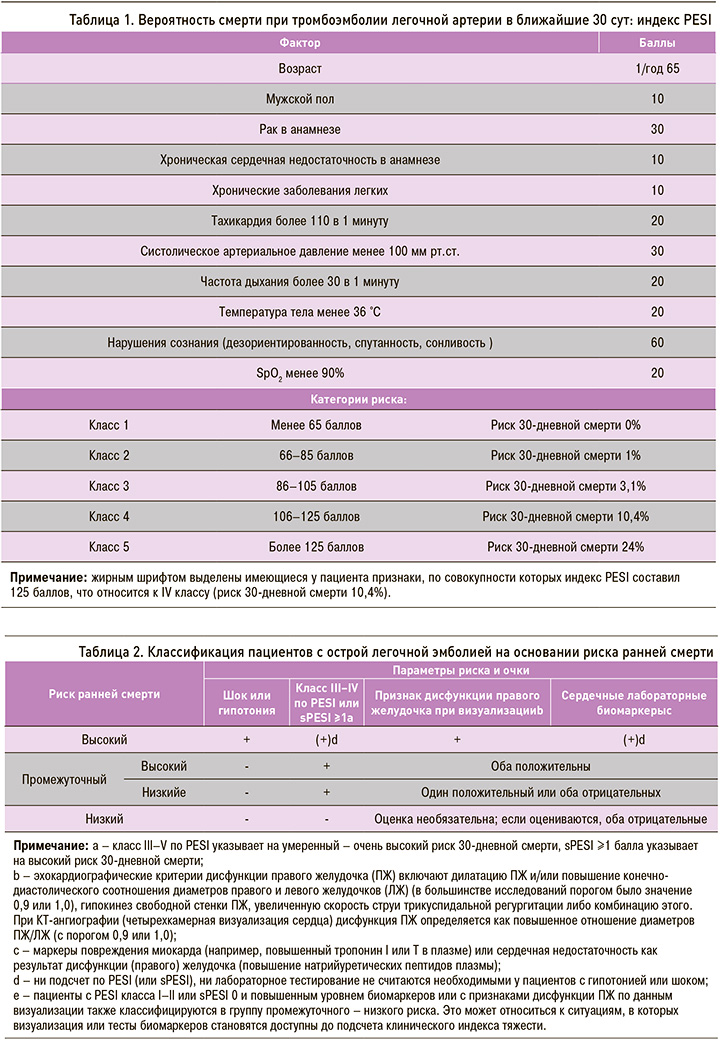

Согласно рекомендациям по лечению ТЭЛА Европейского общества кардиологов от 2014 г. и Российского кардиологического общества от 2015 г. [17, 18], для выбора лечебной тактики необходимо определить вероятность смерти при ТЭЛА в ближайшие 30 сут по индексу PESI (Pulmonary Embolism Severity Index) (табл. 1) и категорию риска (табл. 2).

У пациента В. не было гипотонии, но имелся IV класс риска по PESI, т.е. высокая ожидаемая смертность (4,0–11,4%), эхокардиографические признаки дисфункции правого желудочка без повышения уровня сердечных биомаркеров, что соответствовало промежуточному низкому риску.